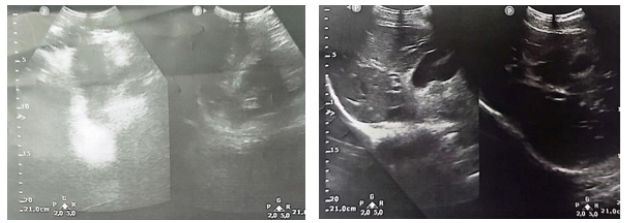

A diagnosis of mild acute pancreatitis was made based on Apache score of 0, BISAP score of 0, Marshall score of 0, and Japanese score of 0. An abdominal ultrasound and lipid profile were requested to investigate the cause of acute pancreatitis. The lipid profile returned normal with total cholesterol at 175mg/dL (HDL 74mg/dL, LDL 93mg/dL, VLDL 8mg/dL, TG 41mg/dL). The abdominal ultrasound showed a normal liver, a distended gallbladder with thin walls, no evidence of gallstones, and non-dilated intrahepatic bile ducts. The common bile duct was of normal caliber, and the pancreas appeared normal in size and echotexture. However, a small amount of fluid was noted in the right paracolic gutter, along with significant distension of intestinal loops with gaseous content in the epigastric area (Figure 1).